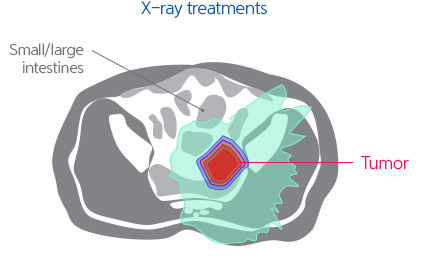

Due to functional and cosmetic reasons, surgical operations may be restrictive. Although high dose radiotherapy is implemented, the level of radiation transferred is limited. Therefore, it is difficult to implement high dose therapy with the X-ray treatments and side effects are common.

For recurrent rectal cancer that has been previously treated with radiotherapy, it is known that tumor removal is difficult and that there are limitations in the cosmetic and functional aspects when treated with surgical operations. Therefore, there are many cases where high dose radiotherapy is implemented. In such cases, even if treated through intensity modulated radiotherapy, side effects from radiation exposure to the surrounding normal organs are common, and for 5 years, the tumor control rate has been less than 50%. However, proton treatment is expected to decrease the level of radiation exposed to the surrounding normal tissues while transferring a high dose of radiation to the tumor for effective removal.